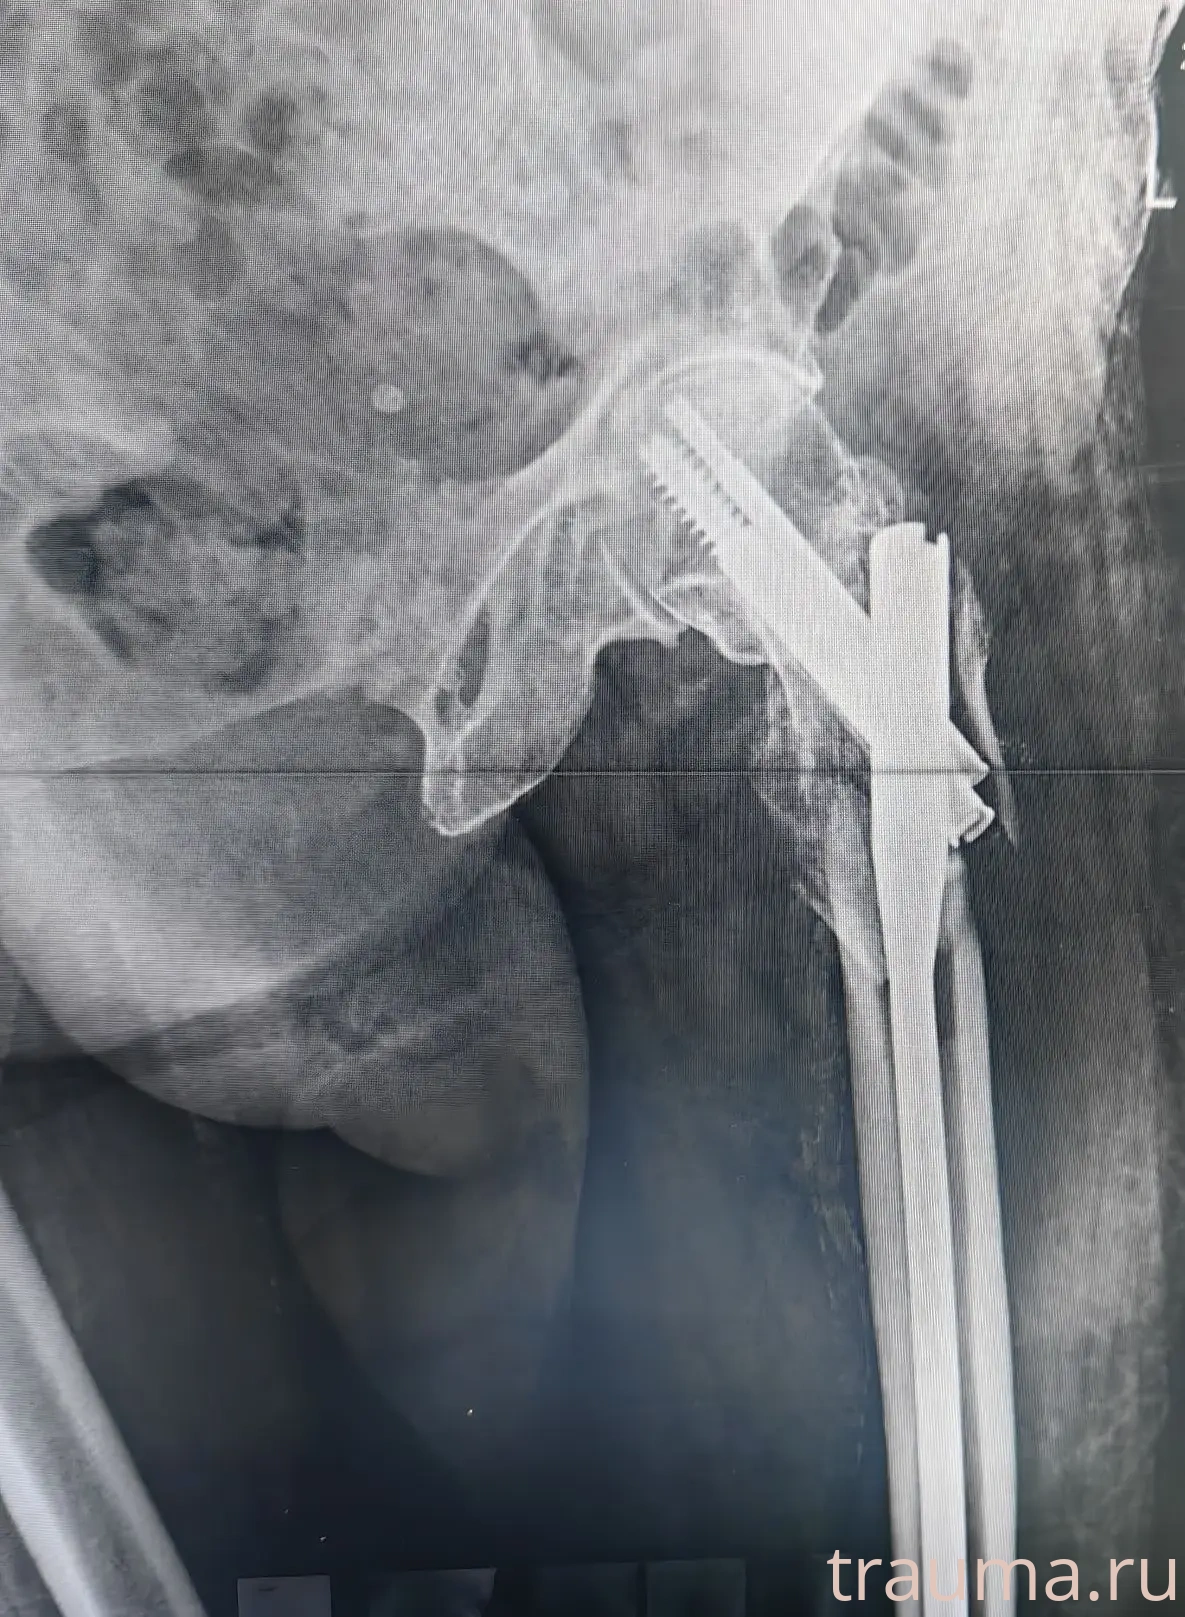

Рентгенограммы

Рентген на дому: по вашему адресу приезжает врач-рентгенолог, травматолог-ортопед с мобильным рентгеновским аппаратом, проводит диагностику травмы или заболевания, делает необходимые рентгенограммы, дает рекомендации по дальнейшему лечению. Получить качественные снимки в домашних условиях возможно благодаря уникальной методике, разработанной МосРентген Центром для института  Склифосовского